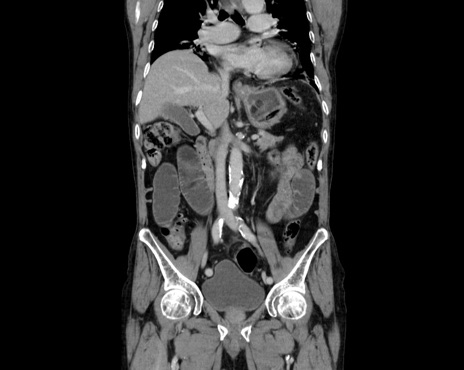

症例26(冠状断像)

【症例】80歳代男性

【主訴】嘔吐

【現病歴】昨晩2回嘔吐あり、今朝になっても嘔吐あり。来院。

【既往歴】胃潰瘍

【身体所見】意識清明、BT 37.6℃、BP 166/95mmHg、HR 100bpm、SpO2 97%、腹部:平坦・軟、腸蠕動音聴取良好、圧痛なし。

【データ】WBC 21900、CRP 1.4